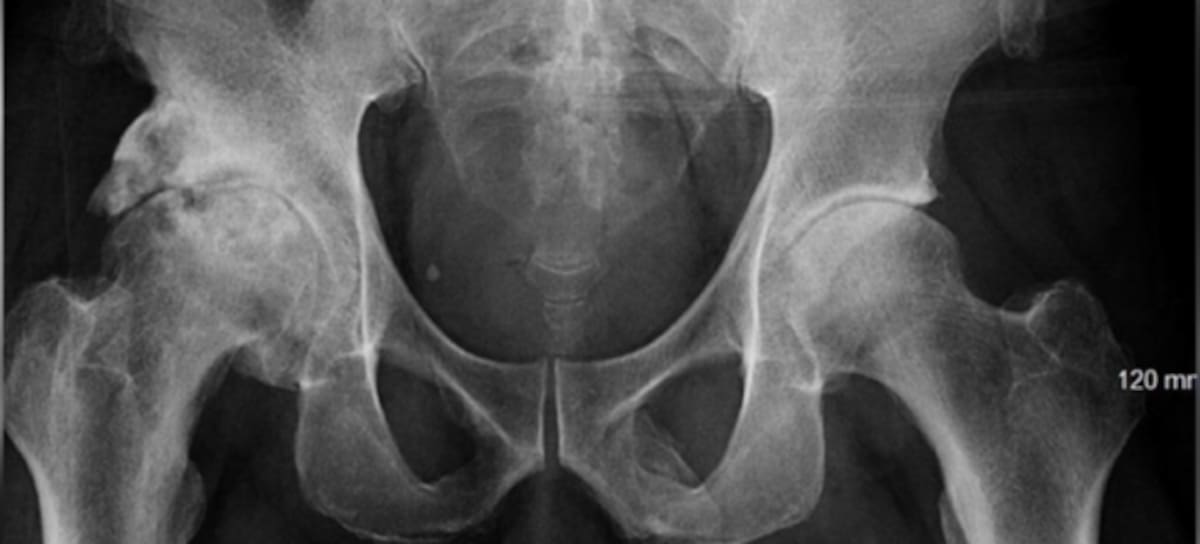

El hombre acudió al Lincoln Medical and Mental Health Center por un dolor en la rodilla izquierda tras un accidente. Los médicos lo encontraron sano, pero el adulto mayor dijo que sentía molestias en el pene. Tras esto, le realizaron una radiografía pélvica que reveló la extraña condición.

Los rayos X mostraron que su miembro genital se estaba osificando, es decir, su pene se estaba convirtiendo en hueso. Esta es una extraña condición de la cual solo se conocen 40 casos en la historia.